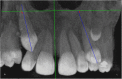

Methods: A cross-sectional study (split mouth design) that included 28 CBCTs (i.e., 56 sides) with unilaterally impacted maxillary canines was performed. After conducting a pilot test to gauge the researcher, heights and widths of skeletal and dentoalveolar variables obtained in the maxilla were measured using coronal and axial views. The angulations of incisors were also measured, and the side with impaction and the unaffected side were compared. Paired sample t test and Wilcoxon signed-rank test were used.

Results: Significant statistical differences (2 mm, p < 0.001) were found between the impacted and non-impacted side measurements from the mid-palatine raphe to the first premolar (proximal alveolar bone crest between the canine (deciduous or permanent) and first premolar); the distance were significantly lower (12.72 ± 2.25 mm) than in the side without impaction (14.67 ± 2.00 mm). Also, the central and lateral incisor angulations showed significant reductions; presenting disto-angulated incisors on the impacted canine side (86.14 ± 7.70° and 74.75 ± 12.67°, respectively) and mesial-angulated incisors on the non-impacted side (91.63 ± 6.79° and 81.21 ± 8.56° respectively). The other skeletal and dentoalveolar measurements showed no significant differences.

Conclusions: The width from the median raphe to the first premolar is lower in the side of maxillary palatal impacted canines than in the side without impaction. Lateral angulations of incisors were disto-angulated on the side of impacted canines. Both conditions have clinical implications in the orthodontic treatment.